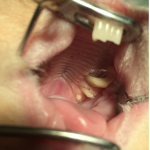

Quand les dents des lapins ne sont plus usées correctement, elles croissent dans la bouche jusqu’à remplir les espaces libres entre les deux mâchoires. Elles exercent alors des forces les unes contre les autres, puis se déforment et changent d’orientation : c’est ce que l’on appelle une malocclusion dentaire.

Il est aussi possible que les dents poussent de façon rétrograde : vers le bas pour les dents inférieures et vers le haut pour les dents supérieures.

Des compressions et lésions de structures proches des structures dentaires